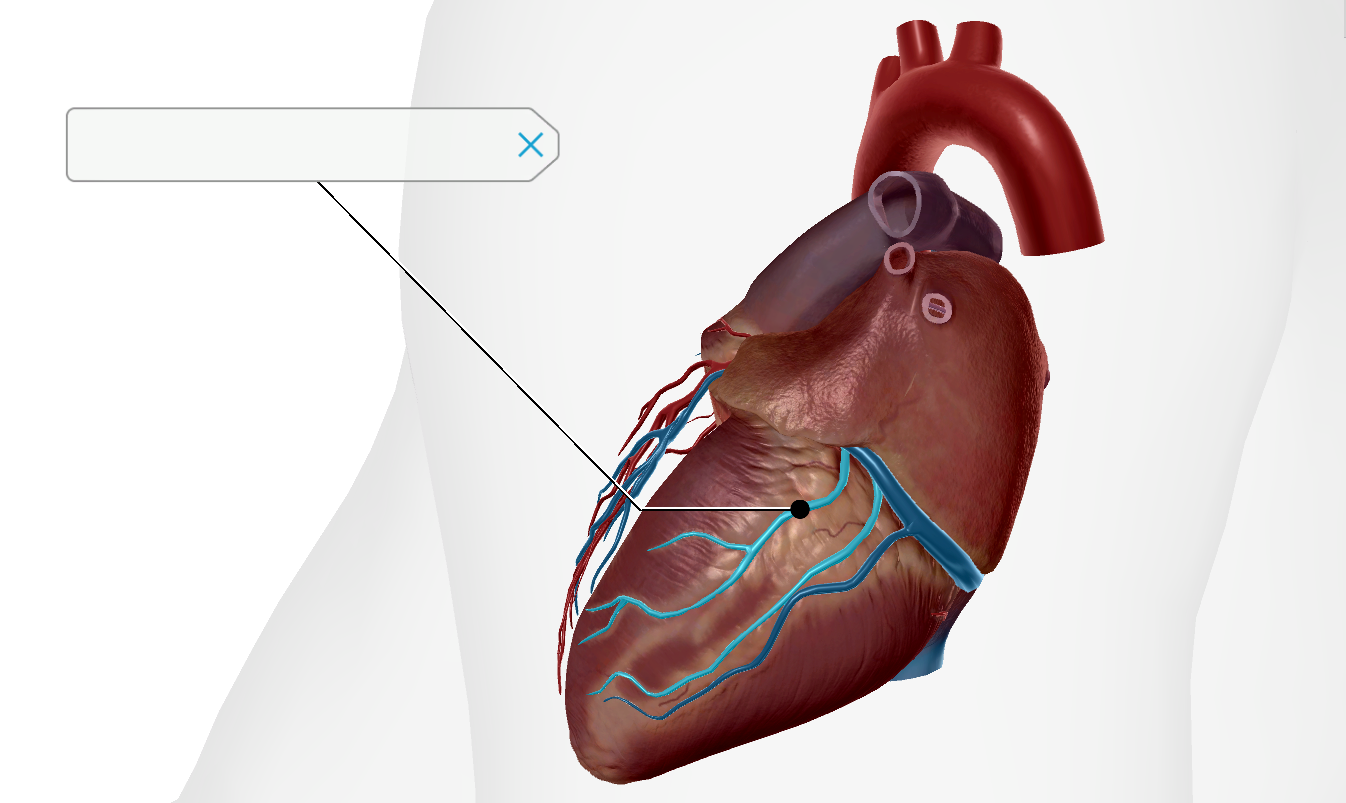

Anterior Interventricular Artery

Circumflex Branch

Coronary Artery

Middle Cardiac Vein

Coronary Sinus

Anterior Interventricular Sulcus

Coronary Sulcus

Small Cardiac Vein

Anterior Cardiac Vein

Posterior Interventricular Sulcus/Artery

Coronary Veins

Marginal Branch

Circumflex Artery

Great Cardiac Vein